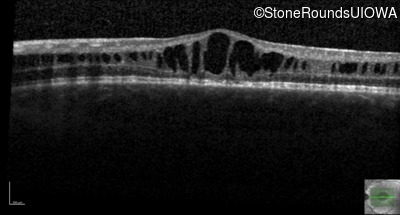

Optical Coherence Tomography - Right - 20/63 -2

Exemplar / OCT Stack

OCT Stack